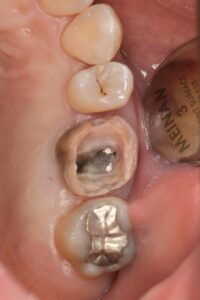

ⅰ.抜髄(過去に神経の治療がされていない歯の治療)の場合

➡むし歯の除去(隔壁作製)、神経の除去と根管内クリーニング、いけたら根管充填とレジンコア(土台)

ⅱ.再治療(過去に治療してる根管)の場合

➡過去の充填物やむし歯の除去と隔壁作製、根管内の充填物の除去とクリーニング

時間に余裕があれば根管充填とレジンコア